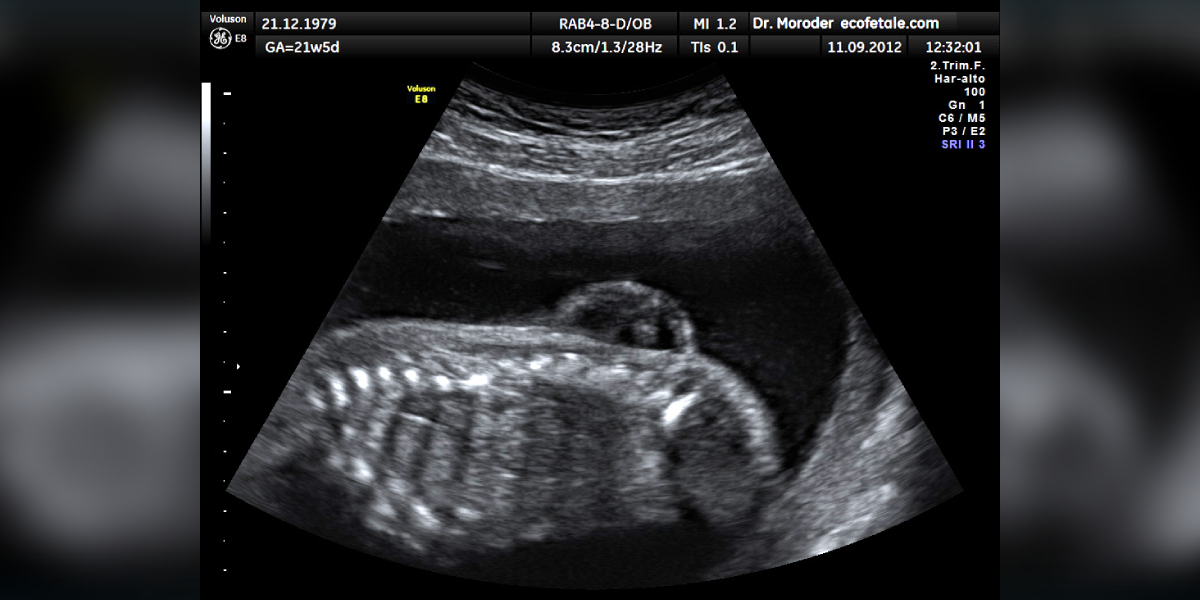

Myelomeningocele in ultrasonography. (Wikimedia Commons)

Myelomeningocele is a type of neural tube defect (NTD) and a congenital condition that occurs when a baby’s backbone (spine) and spinal canal do not close properly before birth.

This birth defect typically develops within the first four weeks of pregnancy. Myelomeningocele is characterised by an incomplete closure of the neural tube (neural tube forms the early brain and spine), resulting in a fluid-filled sac that protrudes from the baby’s back.

Myelomeningocele can be diagnosed prenatally through tests like AFP (alpha-fetoprotein) and an ultrasound.

Elevated AFP levels indicate a higher chance of a defect in the spine and spinal cord. Ultrasound scans during the first and second trimesters provide accurate detection of myelomeningocele.